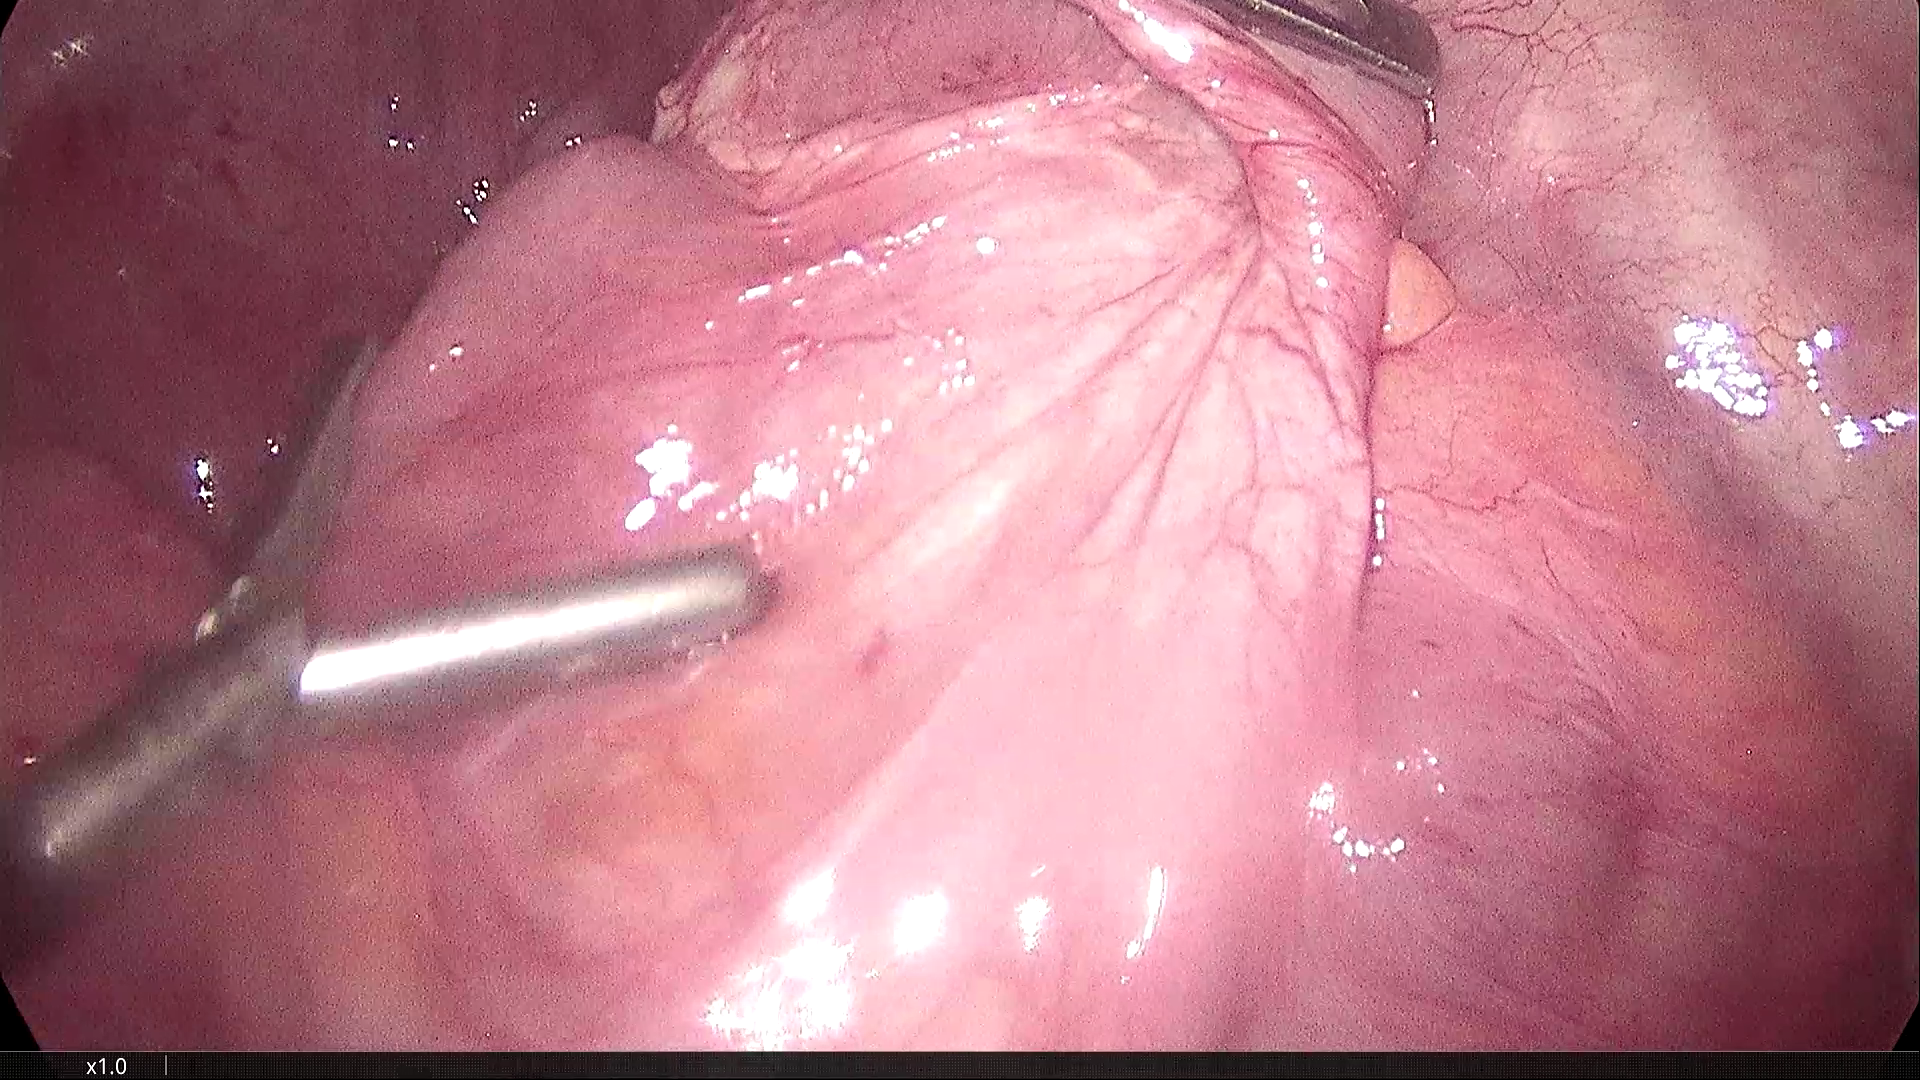

2021-3-31腹腔镜探查,脐部闭合穿刺置入腹腔镜,为观察孔。左下腹及下腹正中分别作操作孔,腹腔镜探查,腹膜光滑,腹腔无积液,胃肠道柔软,空回肠结肠无扩张。无游离大网膜,右下腹无游离肠襻,区域性的回肠肠襻为软膜样组织覆盖包裹,无明显炎症反应。包裹团块张力不高,内侧与乙状结肠系膜呈纤维组织粘连。锐性分离,无明显渗出。自后腹壁锐性切开包膜,显露其内迂曲回肠襻,形态大致正常,与包膜呈一般纤维组织性间隙,易于分离。包膜内肠管间有数条致密粘连纤维索带,予以切除。切除大部包膜组织,完全解放其中的回肠及阑尾远端部分。局部创面少许渗出,自回盲部顺序近端探查检视所有系膜小肠,见肠管及系膜自然正常形态,肠道畅通,未见憩室、肿物及外压扭转等病变。包膜包裹段回肠120cm,肠壁、系膜柔顺无损伤。直肠及盆腔未见明显异常,置腹腔引流管一根。

末段回肠为纤维软膜包裹

横结肠处大网膜消失,代以纤维软膜样组织。

乙状结肠与回肠襻包裹膜的纤维粘连

包裹回肠襻的纤维膜